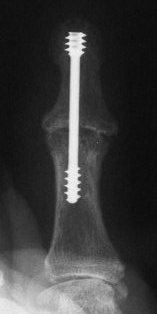

Herbert screw fixation seems most solid if leading threads are in the narrowest segment - the phalangeal neck.